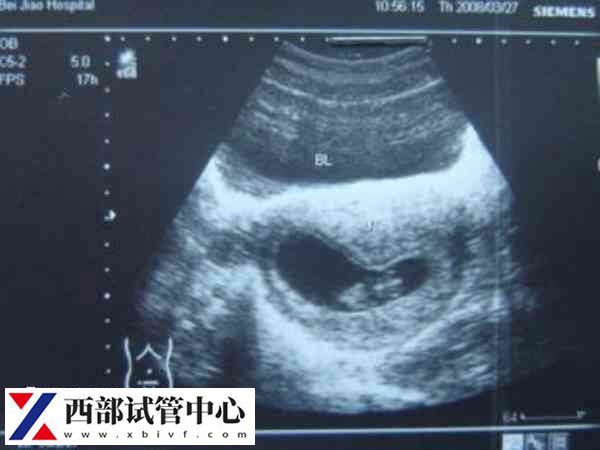

试管移植成功后可以在孕50天左右做第一次b超,这个时候能观察到胎儿是否是宫外孕;孕22至26周做b超能仔细的观察到胎儿的情况;孕28至32周可以做一次全面细致的检查,能够判断胎儿是否存在畸形的情况;足月出生前做b超可以观察胎儿的胎位,对胎儿体重进行预估,有助于为分娩做准备。

刚开始怀孕差不多50天左右,需要通过B超检查受精卵到底是长在宫内,还是宫外,这个时期的b超检查时非常关键的。因为如果是宫外孕,将会引起大出血、威胁到孕妇的生命体征,如果确认在宫内又能够看到胎心,那么胎儿就可以继续生长发育。